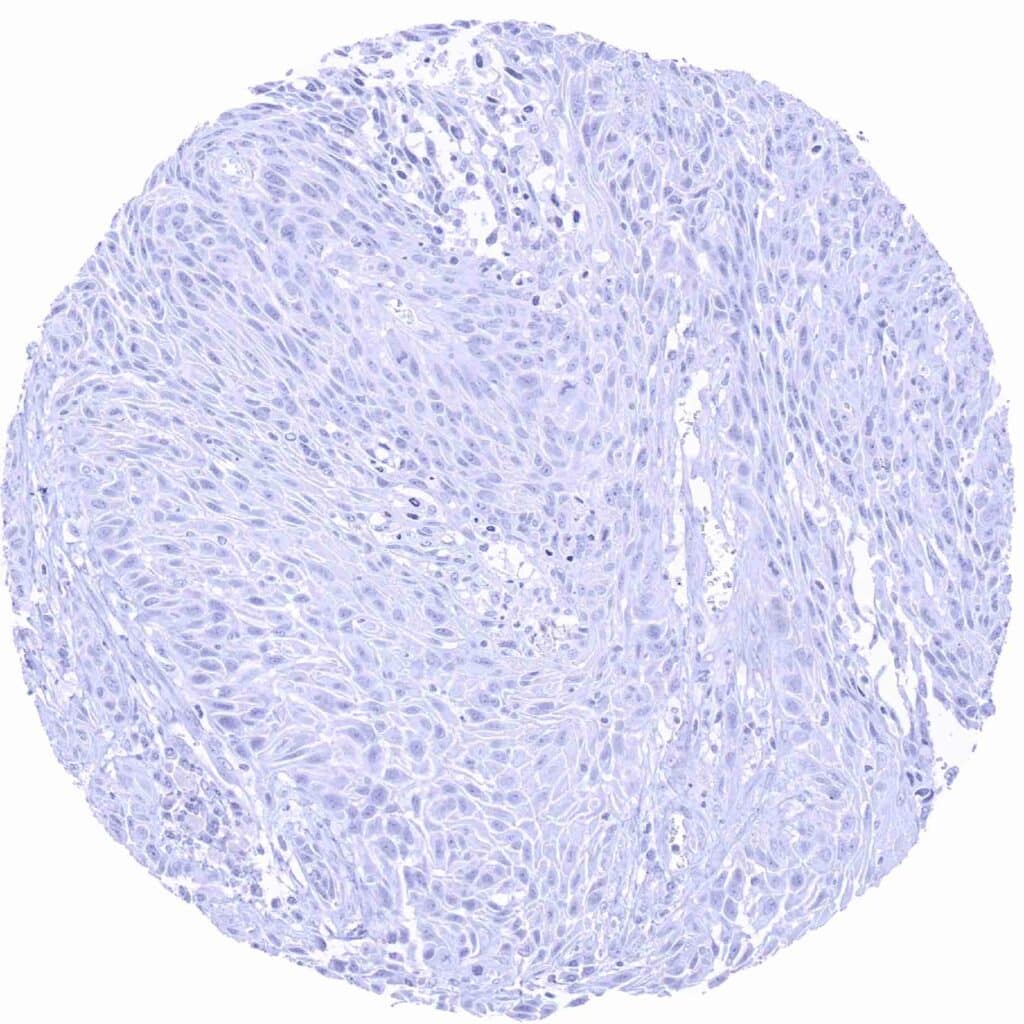

Esophagus – Prostein negative squamous cell carcinoma